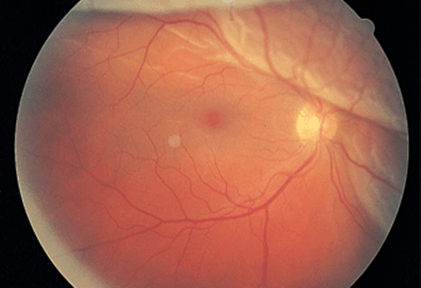

This produces symptoms of floaters, flashing lights, and a scotoma in the peripheral visual field corresponding to the detachment (Fig. 21-14). If the detachment includes the fovea, there is an afferent pupil defect and the visual acuity is reduced. In most eyes, retinal detachment starts with a hole, flap, or tear in the peripheral retina (rhegmatogenous retinal detachment). Patients with peripheral retinal thinning (lattice degeneration) are particularly vulnerable to this process. Once a break has developed in the retina, liquefied vitreous is free to enter the subretinal space, separating the retina from the pigment epithelium. The combination of vitreous traction on the retinal surface and passage of fluid behind the retina leads inexorably to detachment. Patients with a history of myopia, trauma, or prior cataract extraction are at greatest risk for retinal detachment. The diagnosis is confirmed by ophthalmoscopic examination of the dilated eye.

FIGURE 21-14

Retinal detachment appears as an elevated sheet of retinal tissue with folds. In this patient the fovea was spared, so acuity was normal, but a superior detachment produced an inferior scotoma.